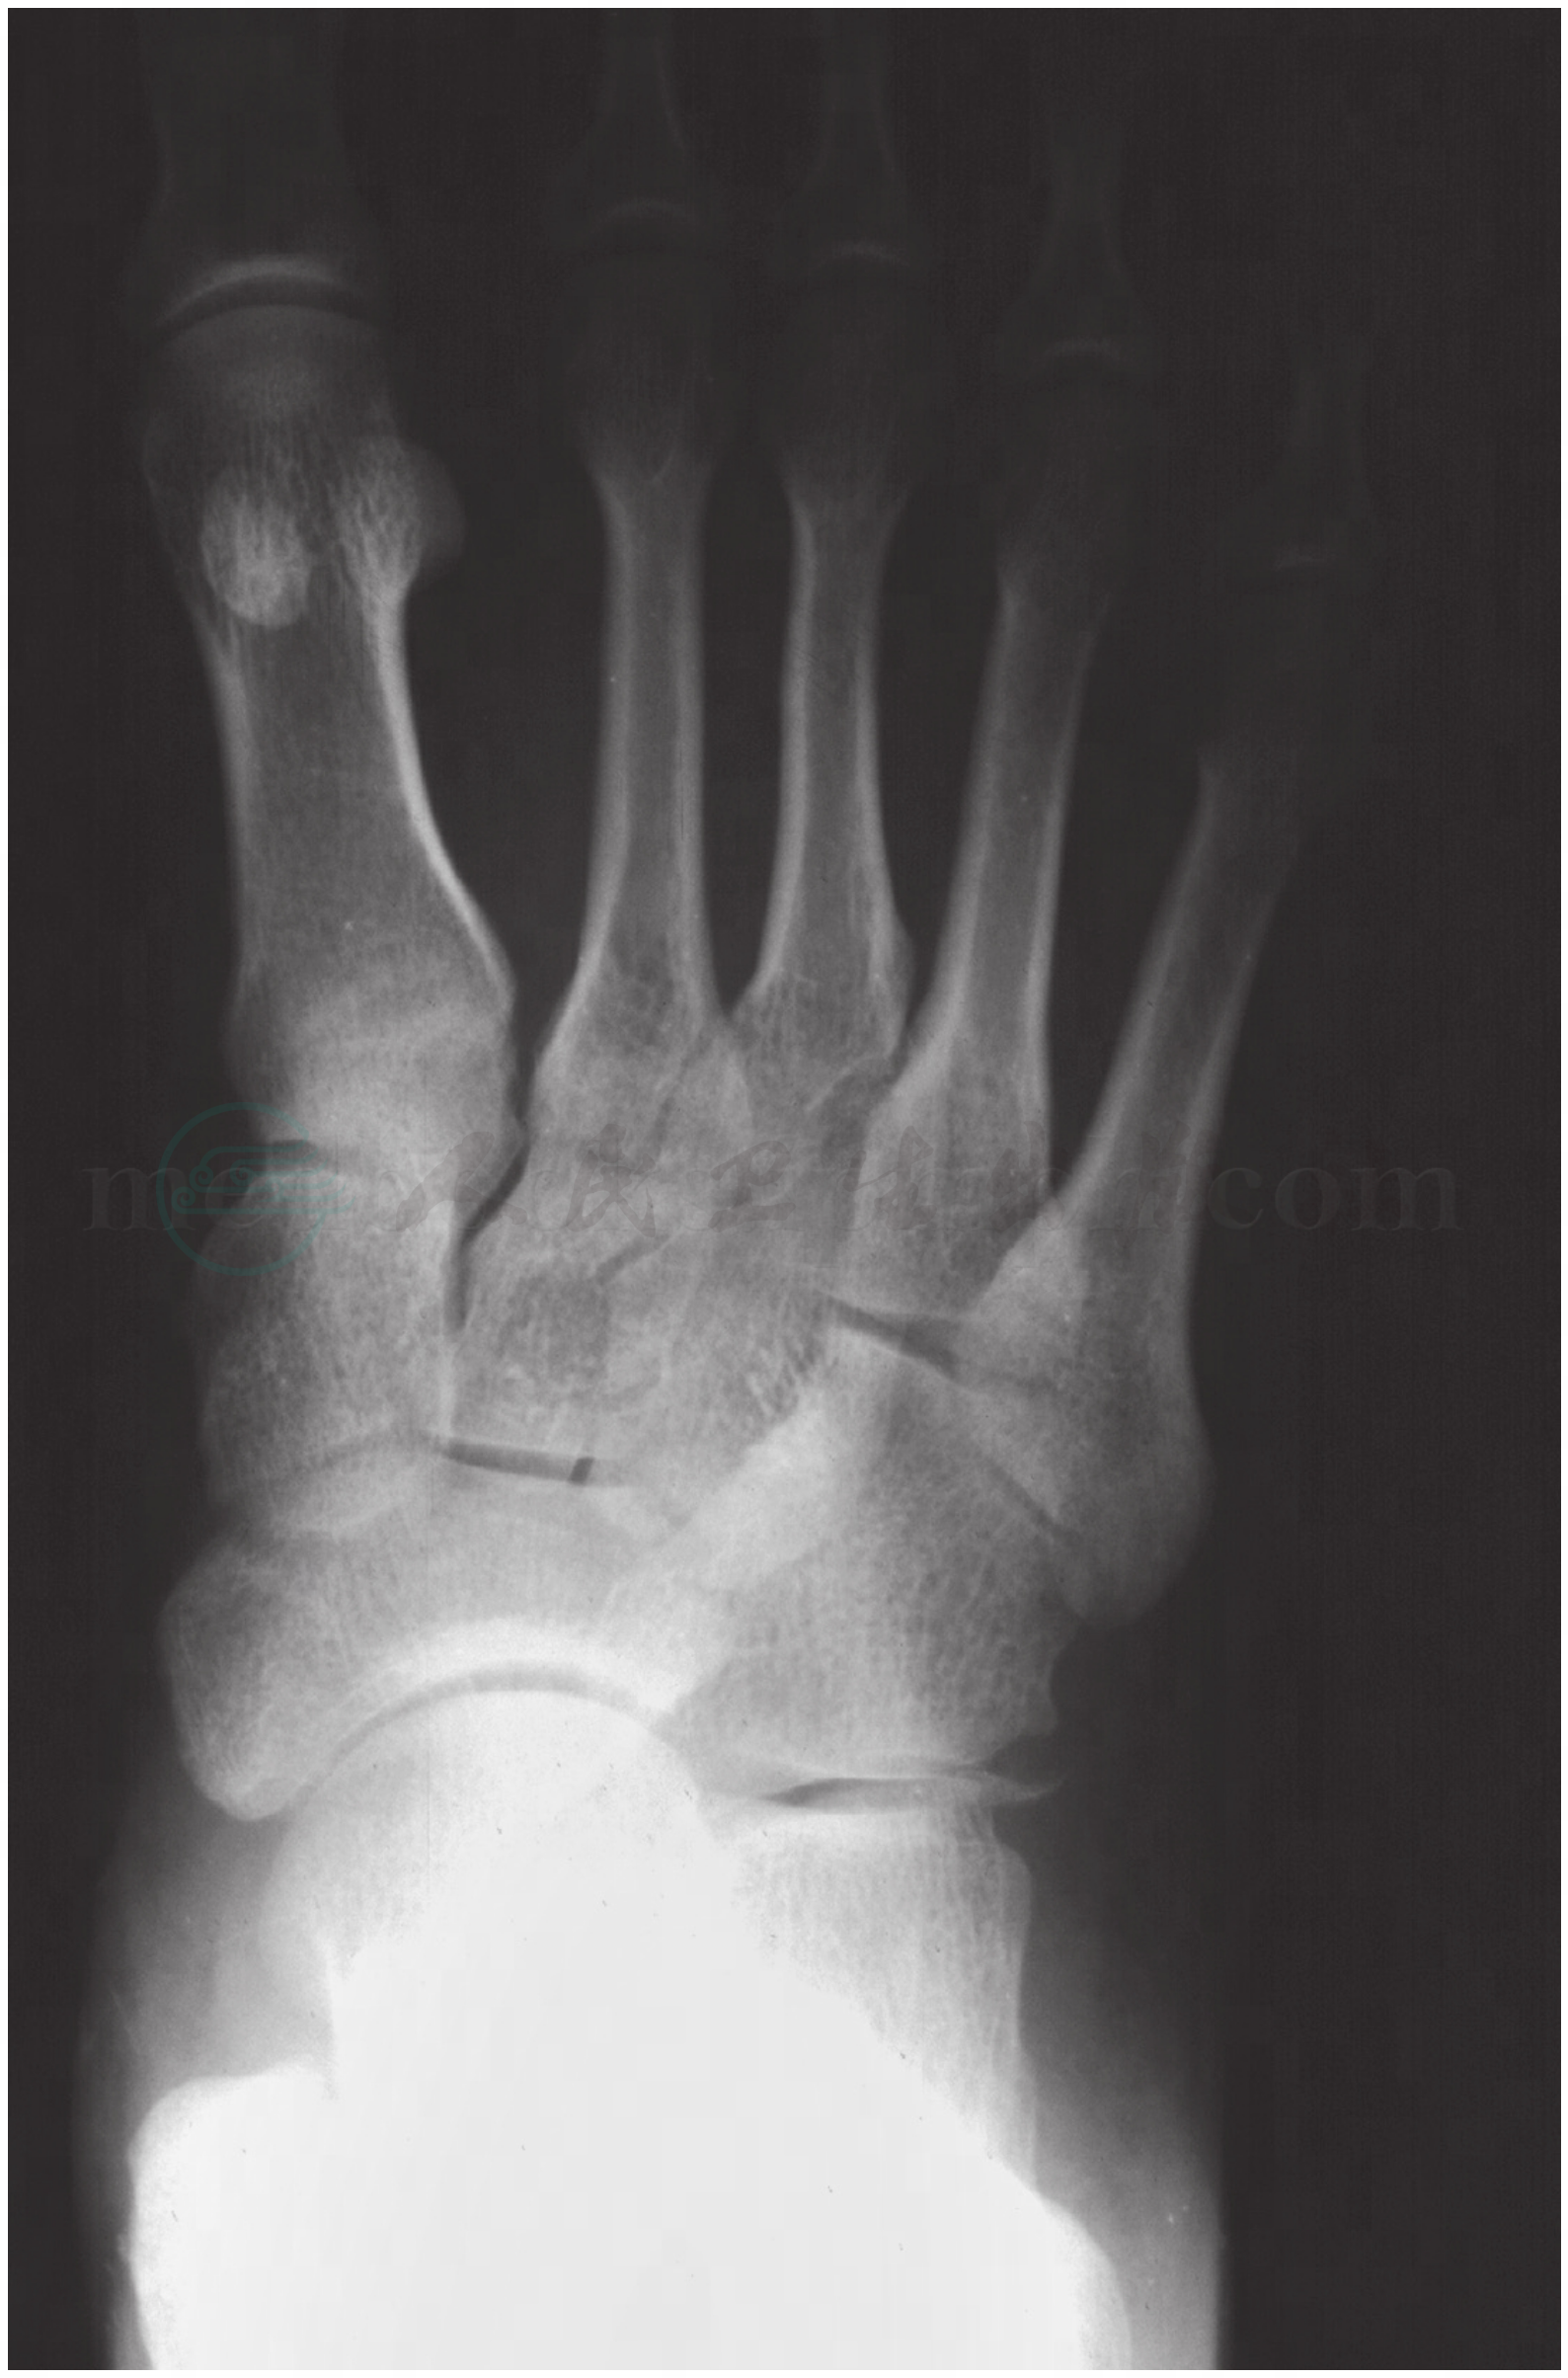

图1 第1楔骨骨折

注:第1楔骨内侧缘撕裂骨折(↑),小骨折片向内侧分离移位,邻近软组织肿胀。